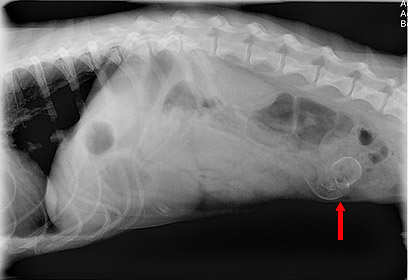

מה הסתתר בבטן של הכלב קולומבו?

קולומבו, כלב מגזע באסט-האונד, בעל חיבה מסוכנת לבליעת גרביים ומזון, שוב הדאיג את בעליו. בעקבות הקאות וחוסר תיאבון, הוא הובהל לטיפול וטרינרי. לא תאמינו מה גילו לו בבטן